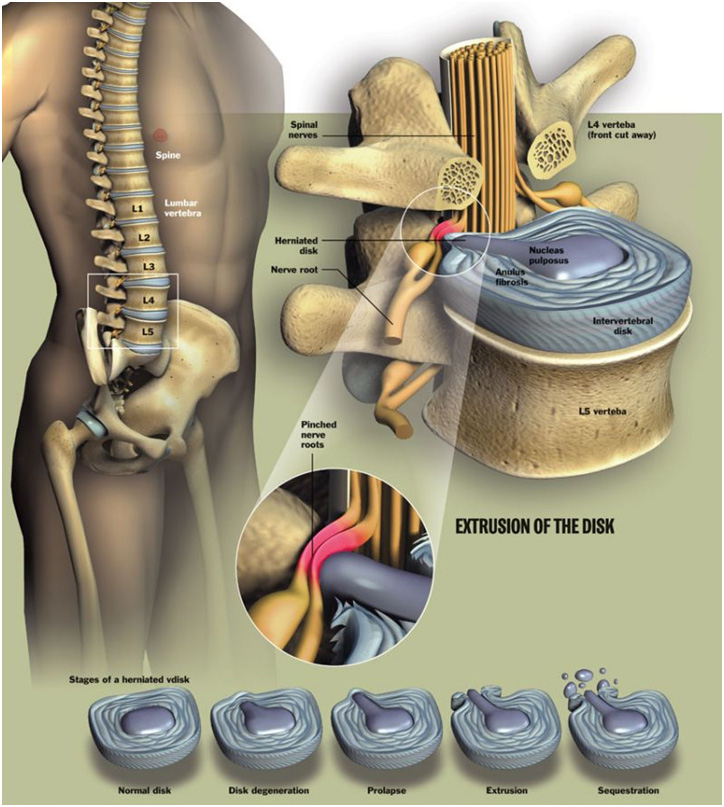

Herniated Disc | Causes, Symptoms, Treatments – Ainsworth Institute

Bulging and Herniated Discs – Explained | Physical Health Care

What is the difference between a bulging disc and a herniated disc?

Herniated Bulging Disc

Lumbar Disc Herniation|Causes|Symptoms|Treatment-Manual Therapy, PT …